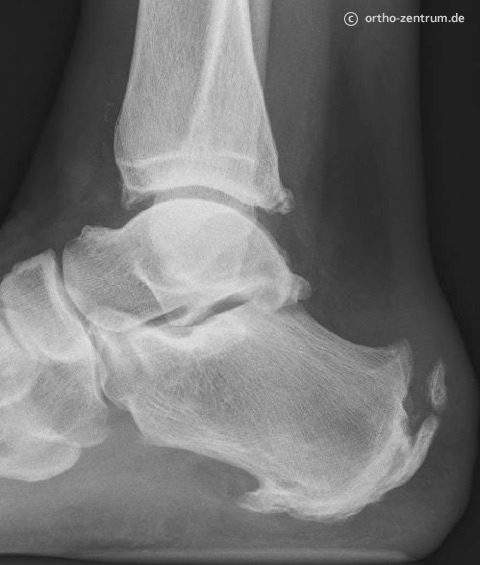

Arthrose und Fehlstellungen der Fußwurzel und des oberen Sprunggelenkes

Bei schmerzhaftem Gelenkverschleiß im Endstadium ist oft die Operation der letzte Ausweg, beispielsweise bei unfallbedingten Fehlstellungen.

Plattfuß

Ein abgeflachtes Längsgewölbe ist die Ursache des Plattfußes. Meist bestehen Schmerzen auf der Innenseite, die Ferse kippt nach außen

und längeres Gehen wird unmöglich. In den meisten Fällen können Einlagen Linderung verschaffen. Differenzierte operative Methoden stehen werden angewandt. Hierbei kann es z.B. nötig sein, das Fersenbein zu durchtrennen und in Korrekturstellung zu verschrauben. Häufig werden solche Eingriffe mit Massnahmen an den Sehnen kombiniert (Sehnentransfer).